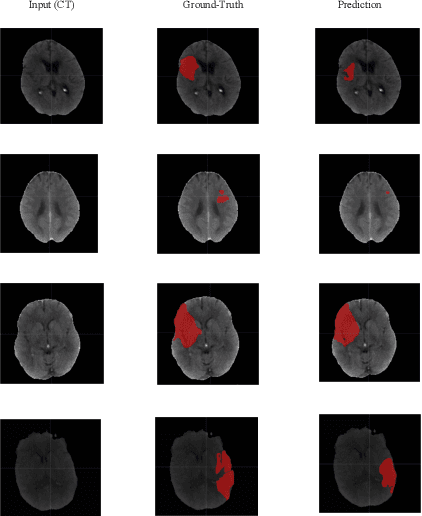

Ischemic stroke occurs through a blockage of clogged blood vessels supplying blood to the brain. Segmentation of the stroke lesion is vital to improve diagnosis, outcome assessment and treatment planning. In this work, we propose a segmentation model with adversarial learning for ischemic lesion segmentation. We adopt U-Net with skip connection and dropout as segmentation baseline network and a fully connected network (FCN) as discriminator network. Discriminator network consists of 5 convolution layers followed by leaky-ReLU and an upsampling layer to rescale the output to the size of the input map. Training a segmentation network along with an adversarial network can detect and correct higher order inconsistencies between the segmentation maps produced by ground-truth and the Segmentor. We exploit three modalities (CT, DPWI, CBF) of acute computed tomography (CT) perfusion data provided in ISLES 2018 (Ischemic Stroke Lesion Segmentation) for ischemic lesion segmentation. Our model has achieved dice accuracy of 42.10% with the cross-validation of training and 39% with the testing data.